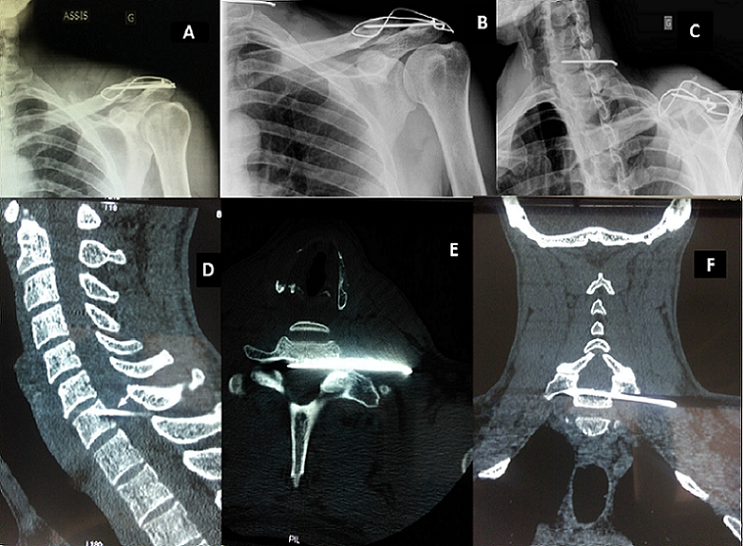

Migration d’une broche dans le canal médullaire cervical après une ostéosynthèse de l’articulation acromio-claviculaire

Il s'agit d'un patient de 49 ans, droitier, cuisinier, victime d'un traumatisme de l'épaule gauche au football. Le diagnostic d'une fracture du quart distal de la clavicule gauche était posé. Il bénéficia d'une ostéosynthèse par embrochage-haubanage. Devant des douleurs et une hypoesthésie avec un déficit des interosseux en territoire C8-T1, le bilan radiographique objectivait une migration de broche au niveau du rachis cervical. Elle transperçait le foramen de conjugaison C7-T1 gauche allant au contact du fourreau médullaire mettant en jeu son pronostic vital ou fonctionnel. L'ablation du matériel d'ostéosynthèse en urgence en Neurochirurgie fut réalisée. L'évolution est marquée par une disparition des névralgies et une récupération fonctionnelle acceptable. L'ostéosynthèse par embrochage-haubanage est une des principales techniques chirurgicales des fractures du quart distal de la clavicule ou des disjonctions acromio-claviculaires. Sa principale complication reste la migration de broche.